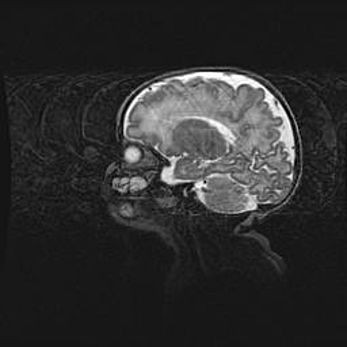

Лейкомаляция с кистозно-глиозной дегенерацией головного мозга.

Возраст: 2 месяца 25 дней

Вес: 6400 г

Окружность головы: 40 см

Срок гестации: 41 неделя

Лейкомаляцию относят к ишемически-гипоксическим повреждениям головного мозга, диагностируемым у новорожденных. При лейкомаляции в головном мозге обнаруживают очаги некроза, возникшие после тяжелой гипоксии и нарушения кровотока. В процессе морфогенеза очаги проходят три стадии: 1) развития некроза, 2) резорбции и 3) формирования глиозного рубца или кисты. Перивентрикулярная лейкомаляция (ПЛ) встречается примерно в 12% случаев среди новорожденных, обычно – у недоношенных детей, причем, частота ее зависит от массы, с которой младенец появился на свет. Наибольшее число малышей страдает лейкомаляцией, если масса при рождении 1500-2500 г.